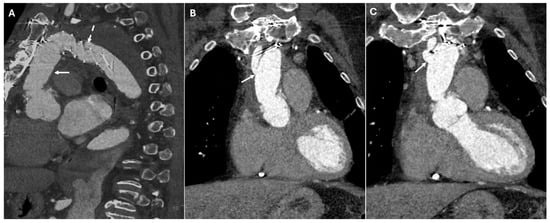

| Elephant Trunk Technique | Staged repair of extensive aortic disease | Open arch graft extending into descending aorta | Floating tubular graft within descending aorta |

| Frozen Elephant Trunk | Single-stage aortic arch + descending repair | Endovascular stent incorporated within open graft | Seamless transition between proximal graft and distal stent |

| Reverse Elephant Trunk | Staged descending arch repair | TEVAR followed by open arch surgery | Combination of open and endovascular grafts |

| Buffalo Trunk Technique | Combined arch and descending aorta repair | Open arch graft with endovascular stent | Hybrid repair with visible proximal graft and extended stent |